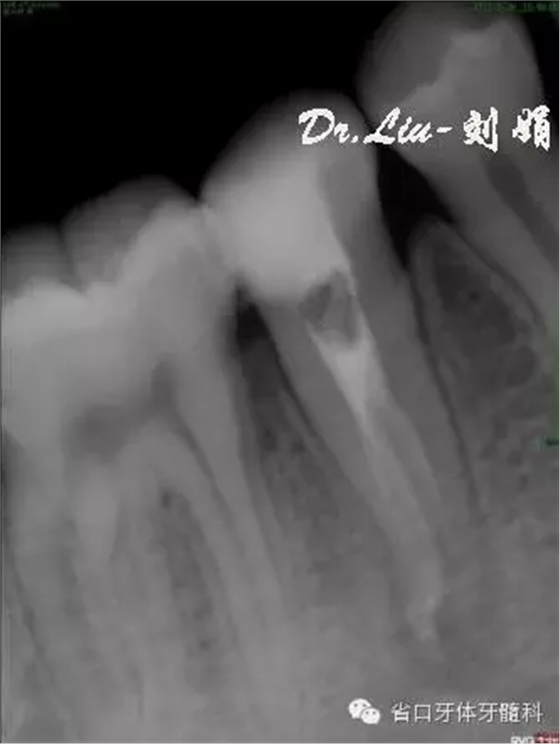

圖5:術(shù)中插尖片,見3根管

45橡皮障隔離下去封藥,清理根管,沖洗,紙尖干燥根管,拍攝試主尖片,顯微鏡下行熱牙膠根管充填,X線片顯示恰填。

圖9:試主尖